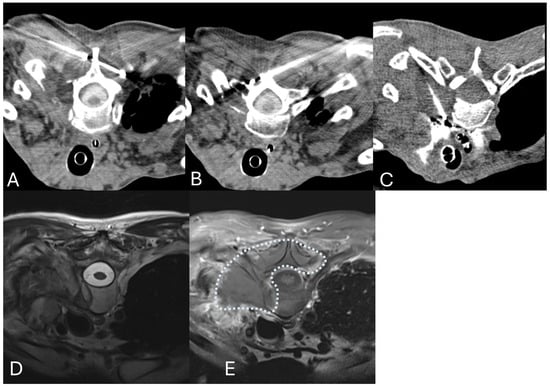

3. Cryoablation

- Cazzato, R.L.; Jennings, J.W.; Autrusseau, P.-A.; De Marini, P.; Auloge, P.; Tomasian, A.; Garnon, J.; Gangi, A. Percutaneous image-guided cryoablation of spinal metastases: Over 10-year experience in two academic centers. Eur. Radiol. 2022, 32, 4137–4146. [Google Scholar] [CrossRef]